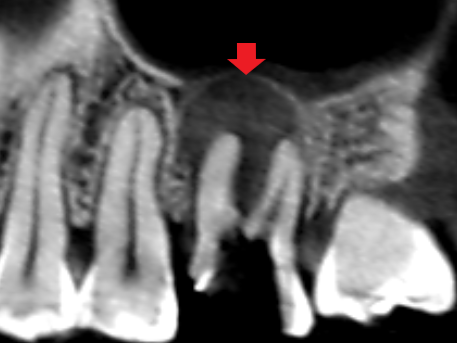

実際に「根管」の画像をご覧頂きましょう。歯の中にある黒い筋が根管です。